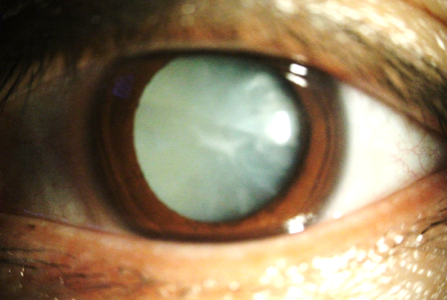

수정체가 김 서린 창문처럼 혼탁해지면서 시력이 저하되는 질병입니다.

시야가 안개가 낀 듯 뿌옇게 보이고, 가까운 물체·먼 물체 둘다 안보이게 됩니다.

이외에도 사물이 겹쳐 보이는 복시, 빛번짐, 눈부심 등의 증상이 생길 수 있습니다.

백내장의 원인으론 선천성요인과 후천성요인이 있으나, 후천성요인이 대부분입니다.

후천성요인 중 노인성, 외상성, 당뇨병성 원인이 가능하고,

그 중에서도 노인성이 대부분입니다.